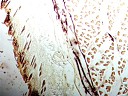

《神经末稍与经络的关系》文琛著 |

大鼠环跳穴皮下组织铺片,胆碱酯酶反应,在脂肪细胞下方有细神经纤维,箭头示脂肪细胞下方有细神经纤维

新明穴皮下组织铺片,胆碱酯酶反应,方框内脂肪细胞与细神经紧邻 |